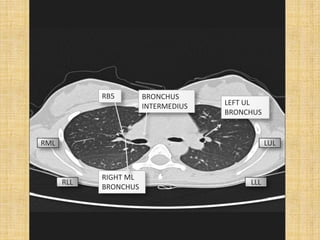

RB2           RB1

RB5        BRONCHUS

INTERMEDIUS   LEFT UL

BRONCHUS

RML                                             LUL

RIGHT ML

RLL                                 LLL